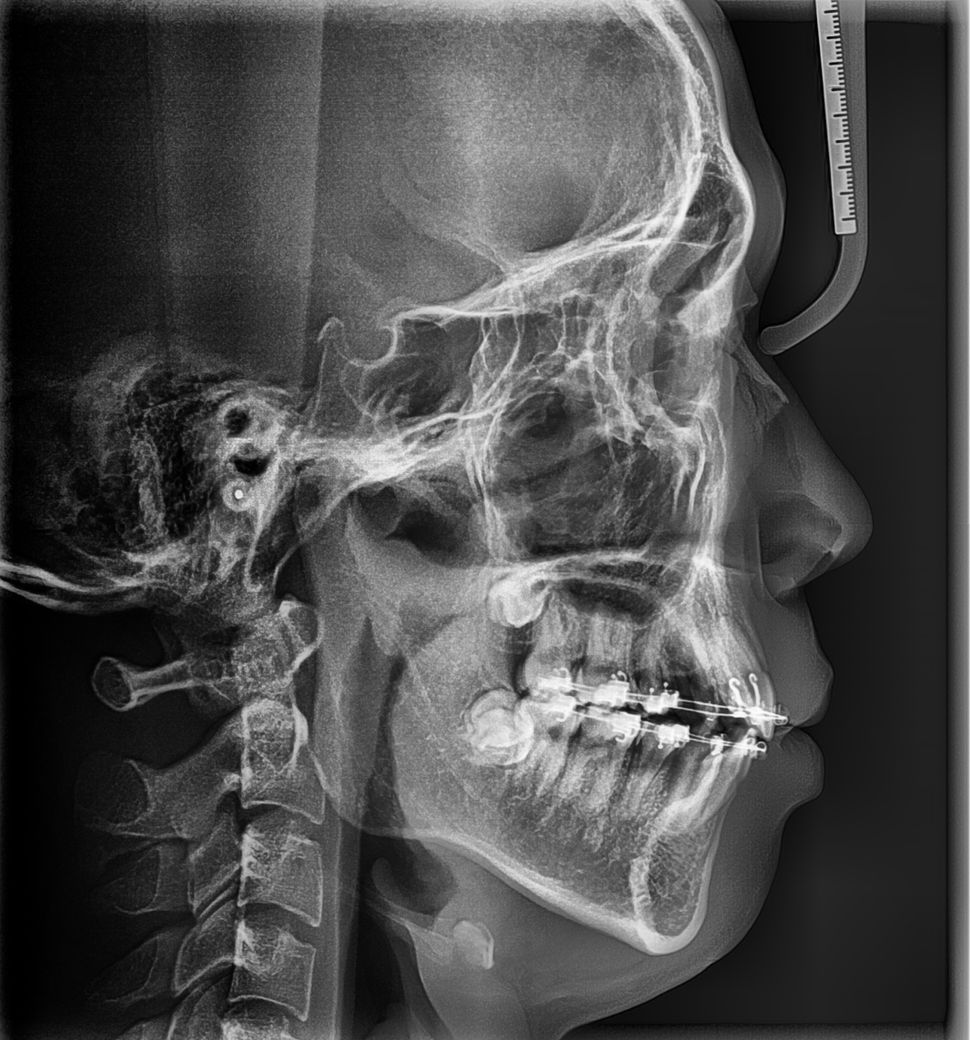

기존교정을 끝냈고 사랑니 발치후 스크류추가교정을 하게되면 치아가 1~2mm정도 뒤로 들어간다는데 입을 들어가게 하고싶어서 하고 싶습니다

다른병원들에서는 된다고 했어요 그렇게 어렵지 않게 이야기 했어요 당긴후에 교합까지 맟출수 있다고 했습니다 현재 병원에서는 교합이 잘못되도 대부분 후에 점점 돌아오지만 그 돌아오는 정도를 만족할지 모르겟다 예측할 수 없다고 하세요 교합조정은 안되는 것 같고요

아래는 현재상태에요 여기서 1~2mm치아가 들어가면 입이 얼마나 들어갈지요..

리스크를 감수하고 해도 될지요

다음은 교정후 현재상태에요